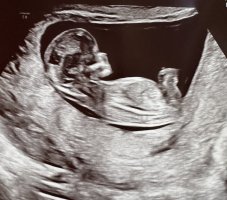

Jeg gjetter også tidlig jente, nuben kan reise seg endaNoen som vil gjette her? Tidlig ultralyd 12+2Vis vedlegget 415499

Spennende! Jeg skal oppdatere her når vi har vært på oulTidlig jente![]()

Takk for svar! Jeg skal oppdatere her når vi har vært på oulJeg gjetter også tidlig jente, nuben kan reise seg enda